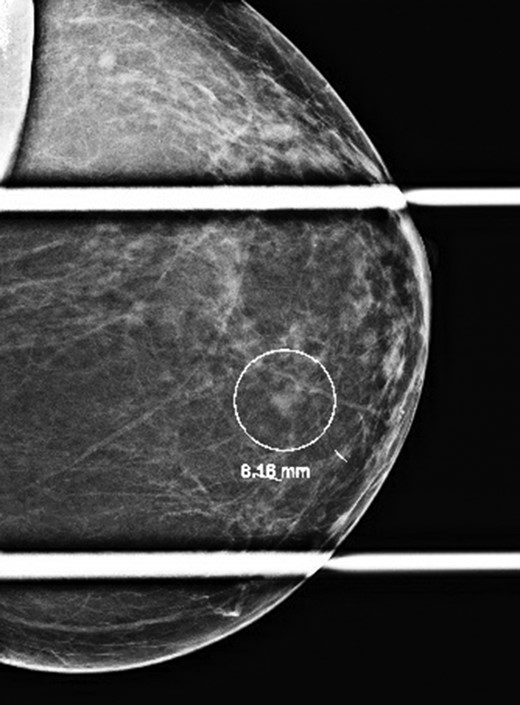

At this most recent visit, physical exam was unremarkable. The patient denied new symptoms including palpable masses, pain, nipple discharge/retraction, skin change, or lymphadenopathy. Diagnostic mammogram was concerning for a suspicious left breast mass (0.6 × 0.5 × 0.5 cm) at the 6:30 position located 4 cm from the nipple and categorized as BI-RADS 4 (Fig. 1). The mass was biopsied, and tissues sent to pathology for diagnosis. The morphology was consistent with the patient’s previous carcinoid tumor (Fig. 2), and tissues stained positive for CD56, CDX2, Chromogranin, and Synaptophysin (Fig. 3). Additionally, tissues were negative for CD117, Estrogen/Progesterone receptors (ER/PR), GCDFP, HER2-Neu, p63, and TTF-1. The tumor had a low proliferative index, with >2 mitoses per high power field. These findings supported a diagnosis of a metastatic, well-differentiated, Grade 2/3 neuroendocrine tumor.

Diagnostic mammogram revealing a BI-RADS 4 left breast mass at the 6:30 position 4 cm from the nipple.